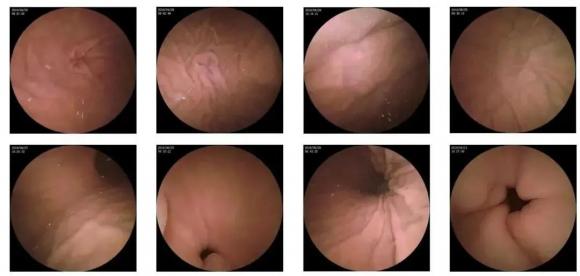

10—15分鐘即可完成賁門、胃底、胃體、胃角、胃竇、幽門等解剖部位觀察,讓胃部檢查更高效。更為重要的是,檢查全程無痛、無創(chuàng)、無麻醉,避免了傳統(tǒng)插管胃鏡帶來的生理痛苦。

二、高清圖像,精確診斷

膠囊機器人的專利三鏡片鏡頭,可深入觀察0.04毫米微小單位,每秒可拍高達4張高清醫(yī)學照片。

醫(yī)生通過智能閱片系統(tǒng),可自動對海量圖像識別過濾,智能篩選,能有效提升醫(yī)生檢查及閱片效率。

任何細微的胃部病變,如胃潰瘍、胃出血、息肉等都無所遁形,盡在大圣磁控膠囊式內(nèi)窺鏡系統(tǒng)的掌握之中。